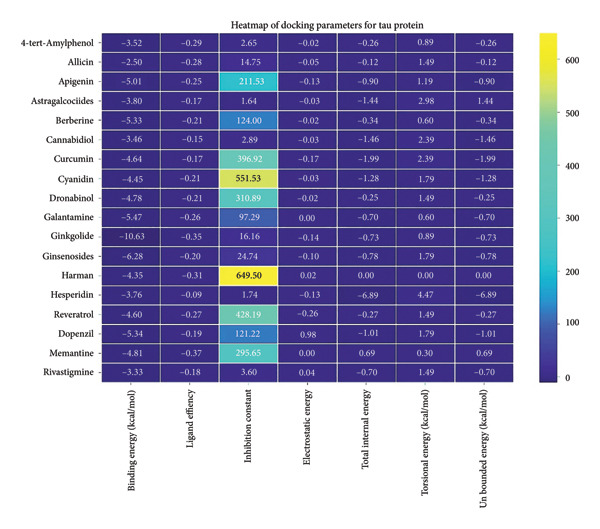

For the tau protein repeat domain, ginkgolide recorded a strong binding energy of −10.63 kcal/mol, with a key stabilizing interaction involving HIS329. This interaction was characterized by a D–A distance of 3.05 Ǻ and an excellent angle of 170.04°. Other top binding compounds included ginsenosides (−6.28 kcal/mol), also interacting with HIS329 and PRO364, and galantamine (−5.47 kcal/mol), forming bonds with VAL337 and VAL339. Berberine bound at −5.33 kcal/mol via GLN351. Apigenin exhibited favorable interaction with the tau repeat domain via a hydrogen bond with ILE 328 (D–A: 2.91 Ǻ; angle 161.21°), highlighting the high quality of the interaction. Among the reference drugs, donepezil bound at −5.34 kcal/mol. Figure 5 details the binding characteristics for tau protein.

The heatmap in Figure 6 provides a comprehensive visual interpretation of the AutoDock Vina docking analysis of natural ligands (light blue‐coded) and reference drugs (orange‐coded) against four key AD‐related receptors. Ginkgolide consistently demonstrates strong (deep red coloration) binding energies across all four receptors: sortilin (blue‐coded), clusterin (green‐coded), Aβ peptide (yellow‐coded), and tau proteins (purple‐coded). Natural ligands exhibited varied yet significant binding profiles; ginsenosides showed strong affinities for tau proteins and Aβ peptide, with moderate binding to sortilin and clusterin. Dronabinol displayed particularly strong interactions with sortilin and Aβ peptide, while berberine and apigenin consistently showed favorable binding across multiple targets, underscoring their broad spectrum of action. In stark contrast, hesperidin consistently presented among the weakest binding affinities across most receptors (indicated by blue/lighter colors), suggesting limited direct molecular interaction.